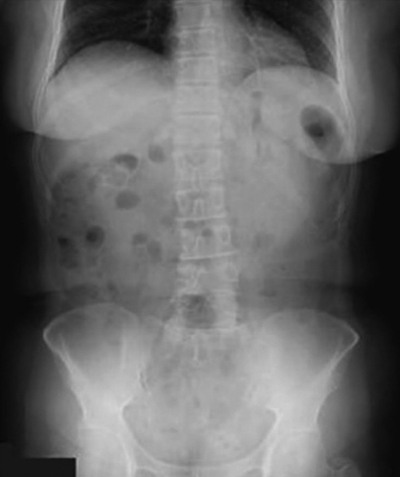

血液所見:赤血球 350万、Hb 11.0 g/dL、Ht 43 %、白血球 9,200、血小板 38 万。血液生化学所見:尿素窒素 19 mg/dL、クレアチニン 1.2 mg/dL。CRP 5.0 mg/dL。立位と臥位の腹部エックス線写真を別に示す。

臥位